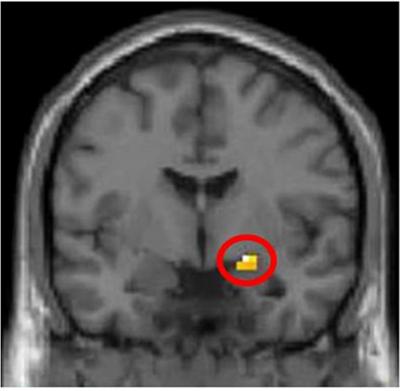

A new study from Karolinska Institutet in Sweden shows that the brain has built-in mechanisms that trigger an automatic reaction to someone who refuses to share. The reaction derives from the amygdala, an older part of the brain. The subjects' sense of justice was challenged in a two-player money-based fairness game, while their brain activity was registered by an MR scanner. When bidders made unfair suggestions as to how to share the money, they were often punished by their partners even if it cost them. A drug that inhibits amygdala activity subdued this reaction to unfairness.

By registering the subjects' brain activity with an MR scanner during play, the researchers were able to see that the brain area controlling these financial decisions was located in the amygdala, an evolutionary old and therefore more primitive part of the brain that controls feelings of anger and fear. Previous research has suggested that the ability to analyse and make decisions of a financial nature is located in the prefrontal cortex.

In the present study, the subjects were either given the anti-anxiety tranquilliser Oxazepam or a sugar pill (placebo) while playing the Ultimate Game. The researchers found that those who had received the drug showed lower amygdala activity and a stronger tendency to accept an unfair distribution of the money – this despite the fact that when asked, they still considered the suggestion unfair.

In the control group, the tendency to react aggressively and punish the player who had suggested the unfair distribution of money was directly linked to an increase in activity in the amygdala. A gender difference was also observed, with men responding more aggressively to unfair suggestions than women and showing a correspondingly higher rate of amygdalic activity. This gender difference was not found in the group that received Oxazepam.